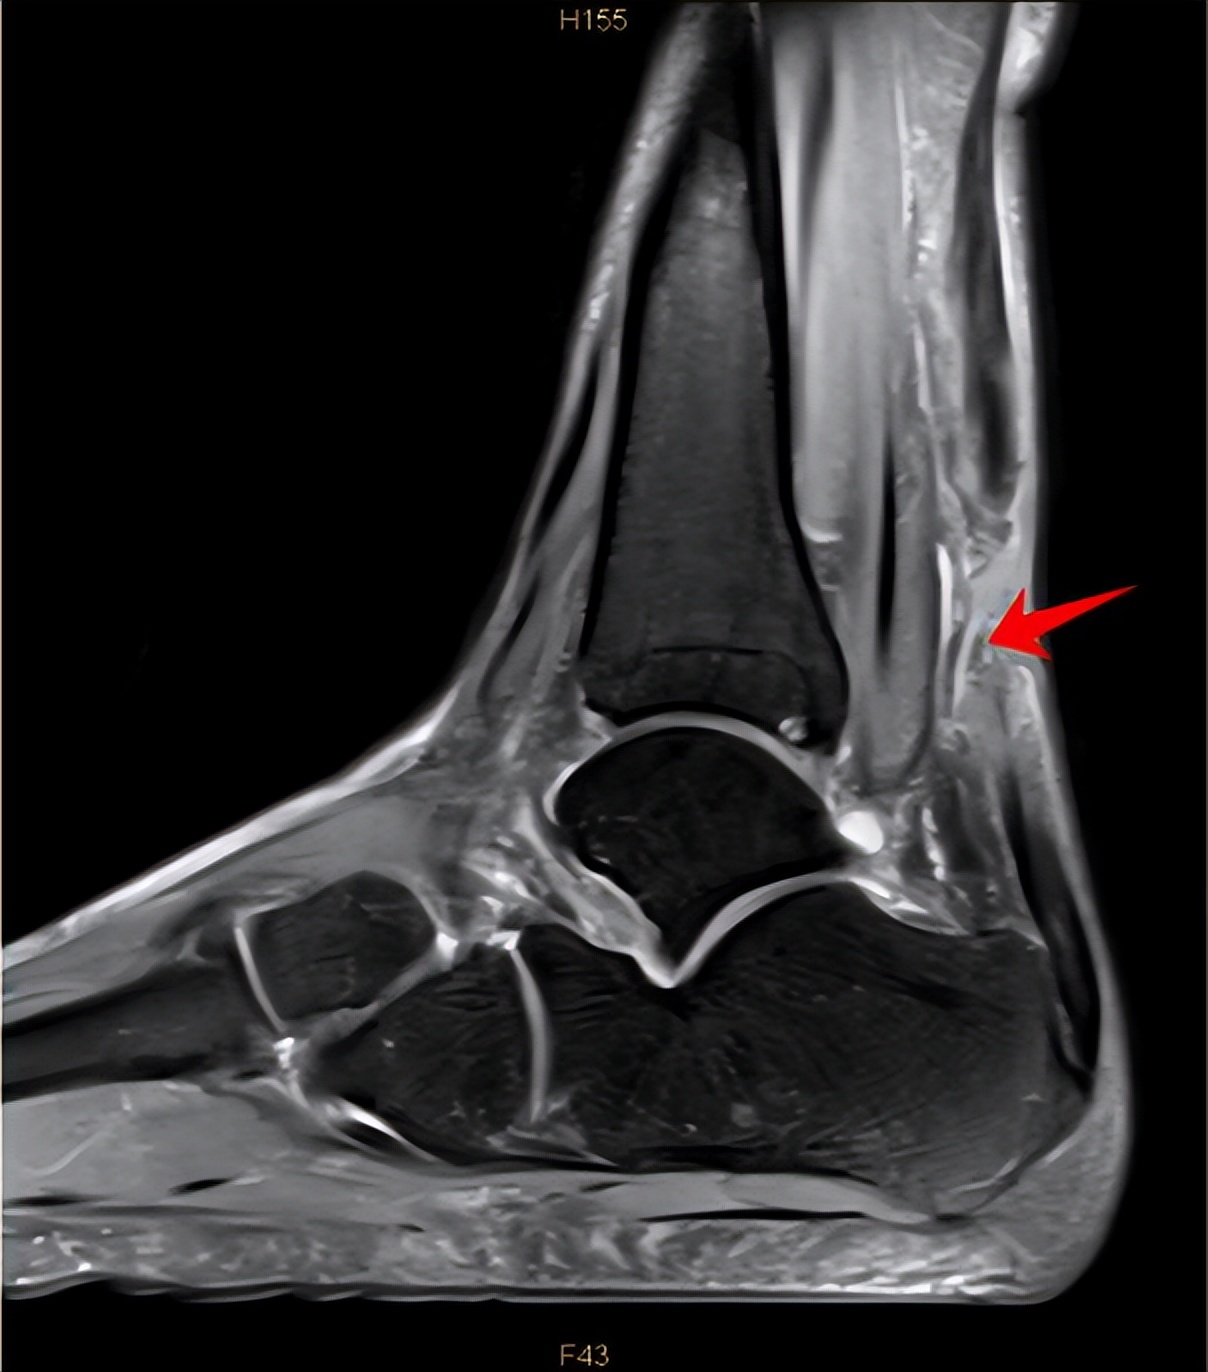

影像学检查在诊断跟腱断裂中也有举足轻重的地位,其中首选的是超声检查,肌腱超声检查是最方便、快捷且实惠的检查方式,具有较高的敏感性,通常作为初步筛查,但需要注意的是,倘若只有部分跟腱断裂,尤其是腱内断裂时,其敏感性就大大降低。而MRI检查对软组织灵敏性较高,可比较准确地显示跟腱及周围软组织情况,明确跟腱是否断裂及断裂的具体位置,且对日后手术具有指导意义。此外,普通X线片可用于判断是否有跟腱附着部位的急性撕脱骨折。